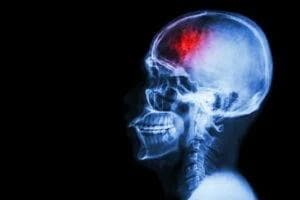

A sudden jolt at a Catalina Highway curve, a workplace fall from a scaffolding plank, or a slip on a grocery aisle can all end with the same life‑altering news: traumatic brain injury. One moment you’re planning weekend hikes in Sabino Canyon; the next, a loved one struggles to remember recent conversations or gets dizzy standing up. Medical visits stack up fast, and steady paychecks can vanish while recovery drags on. If someone else’s negligence set this nightmare in motion, you have the right to ask for help that matches the real cost of a brain injury—not just the first ER bill.

Head trauma can masquerade as simple headaches or fatigue, yet the CDC lists traumatic brain injuries (TBIs) among the leading causes of disability nationwide [1]. Invisible damage often affects: